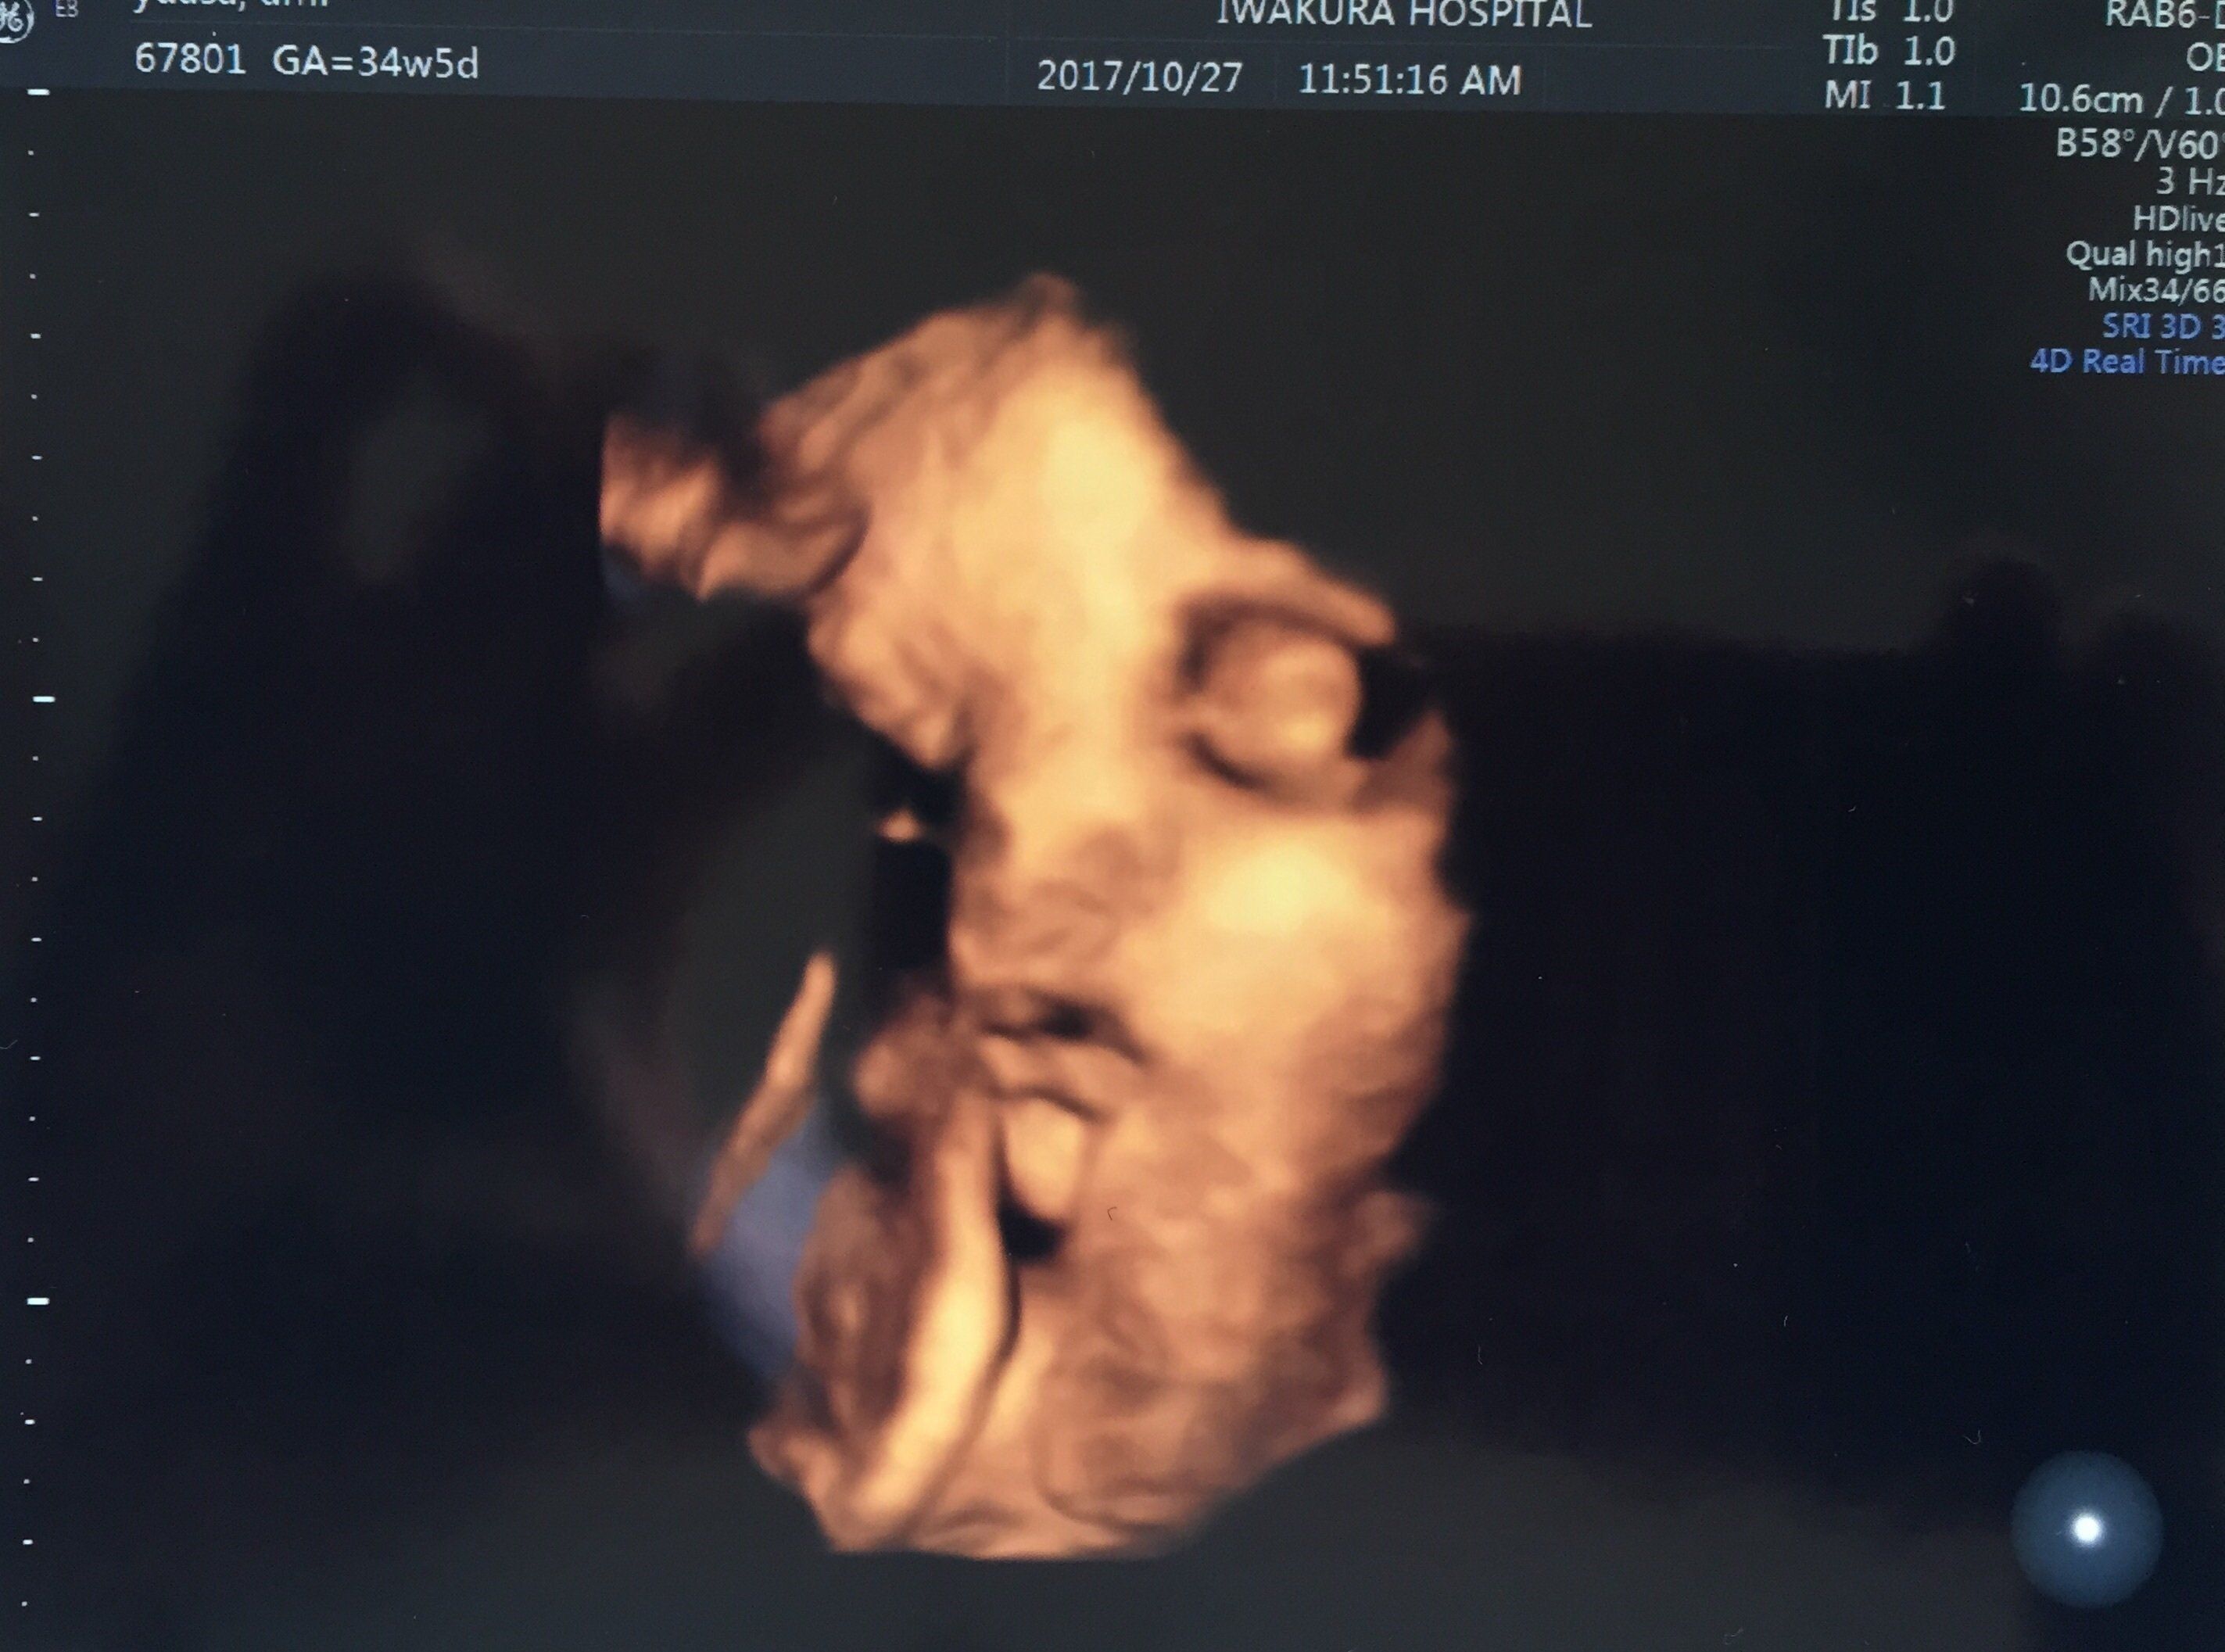

妊娠34週目のエコー写真 妊婦生活いよいよラストスパート!

どうやらおなかの赤ちゃんには、すでに髪の毛がしっかり生えているようで、眉毛もうっすら写っています。頭の髪の毛は黒々して、もう伸びているようにも見えます。頬の肉付きもだいぶ良くなり、顔全体がふっくらしています。この時点で推定体重は2500gを超えており、「少し大きい子だね」と言われていました。長女が2600g代で産まれてきているので、すでに近いサイズの赤ちゃんがおなかにいるのかと思うと、いよいよだと少し緊張しました。

エコー中も手を顔の近くでよく動かしており、顔の一部が手で隠れて黒くなっています。口も少し開いているようです。